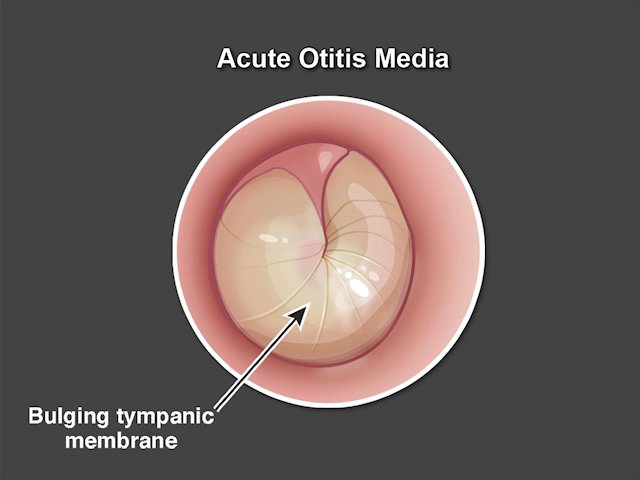

Quick Take video: Treating Acute Otitis Media in Young Children http://nej.md/2gZXNRK pic.twitter.com/jqCIyQYaBd

Can treatment duration for acute otitis media in young children be shortened without changing outcomes? http://nej.md/2hSUhgj

#pediatricspic.twitter.com/dz3vBi9K5D -